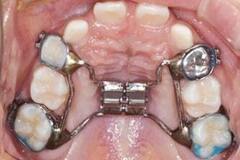

急速拡大装置 上顎の骨に固定する装置で、短期間で顎の幅を広げることを目的とします。特に顎が狭く、歯並びがデコボコしている場合や、交叉咬合の改善に効果的です。